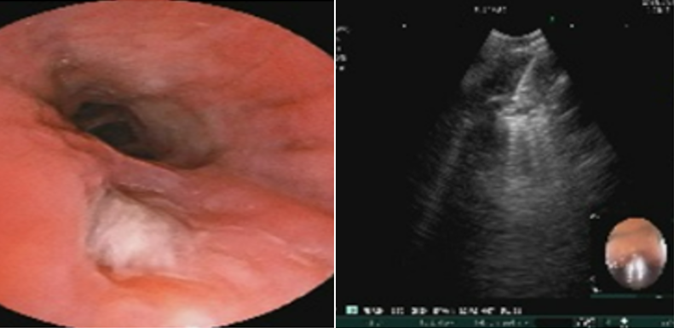

孙武装教授:目前需要进行鉴别诊断。首先,患者咳痰(黄痰)4个月伴咯血,黄痰,提示存在下呼吸道感染,黄痰提示可能为细菌感染。究竟是气道内炎症,还是右肺门病变本身就是炎症,以及是否为混合感染,均有待后续检查确证。其次,右肺门阴影需要进行鉴别。目前检查结果可见CEA升高,通常情况下,CEA升高可能提示腺癌,但右肺门病变多见于鳞癌或小细胞癌,而此种情况CEA一般不会太高。所以从目前的证据分析,我认为肿瘤可以暂时排除。下一步要做强化CT或PET、气管镜检查、EBUS检查等。另外,还需排除淋巴瘤的可能,必要时进行穿刺活检。该患者仍不能除外感染性疾病。检查发现患者有支扩,且倾向于中心型支扩;嗜酸粒细胞升高,但没有过敏性鼻炎,真菌感染的证据缺乏,结核的证据不多,仍需要进一步检查。

BALF检测结果

病理检查

特异性IgE